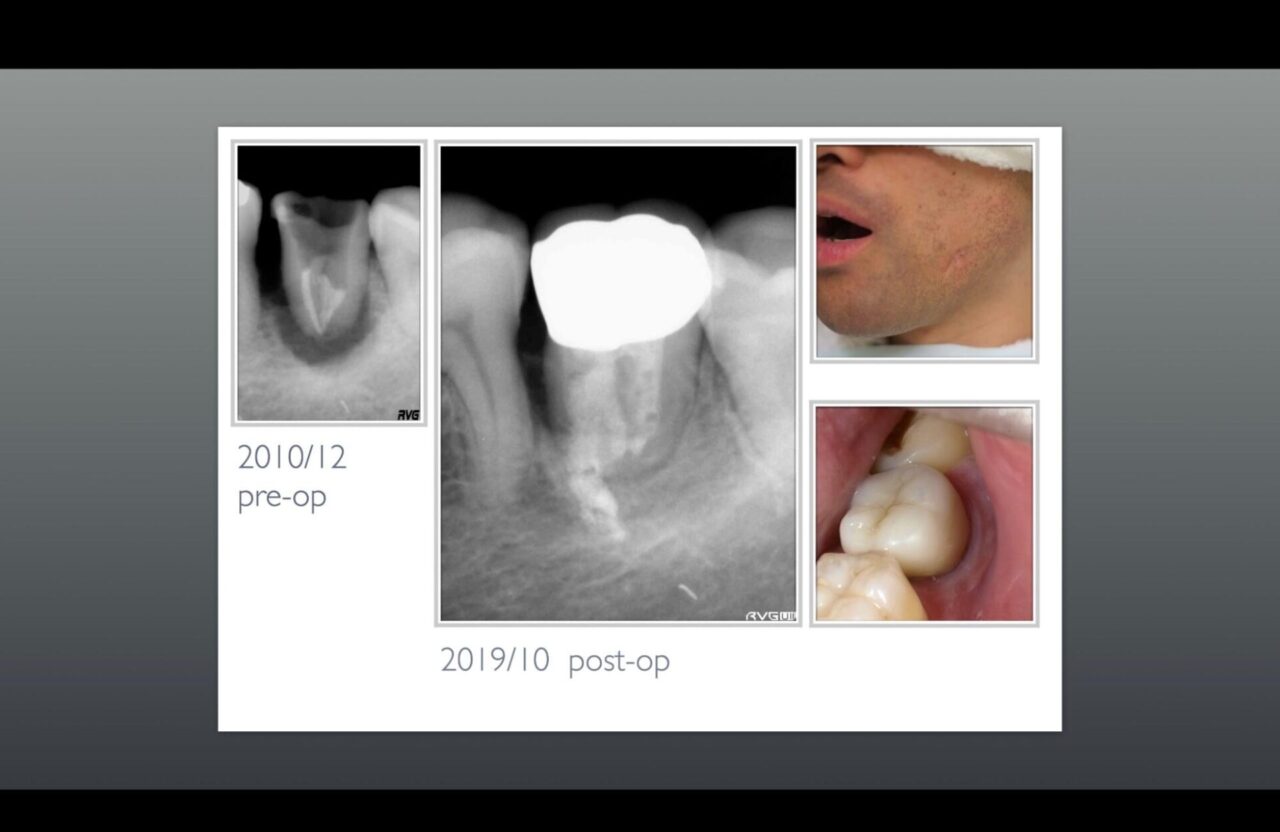

術後経過観察時のレントゲン写真及び口腔内写真、頬のサイナストラクトの跡の写真

根尖側はもちろん、近心側の骨も再生されている事が確認できる。